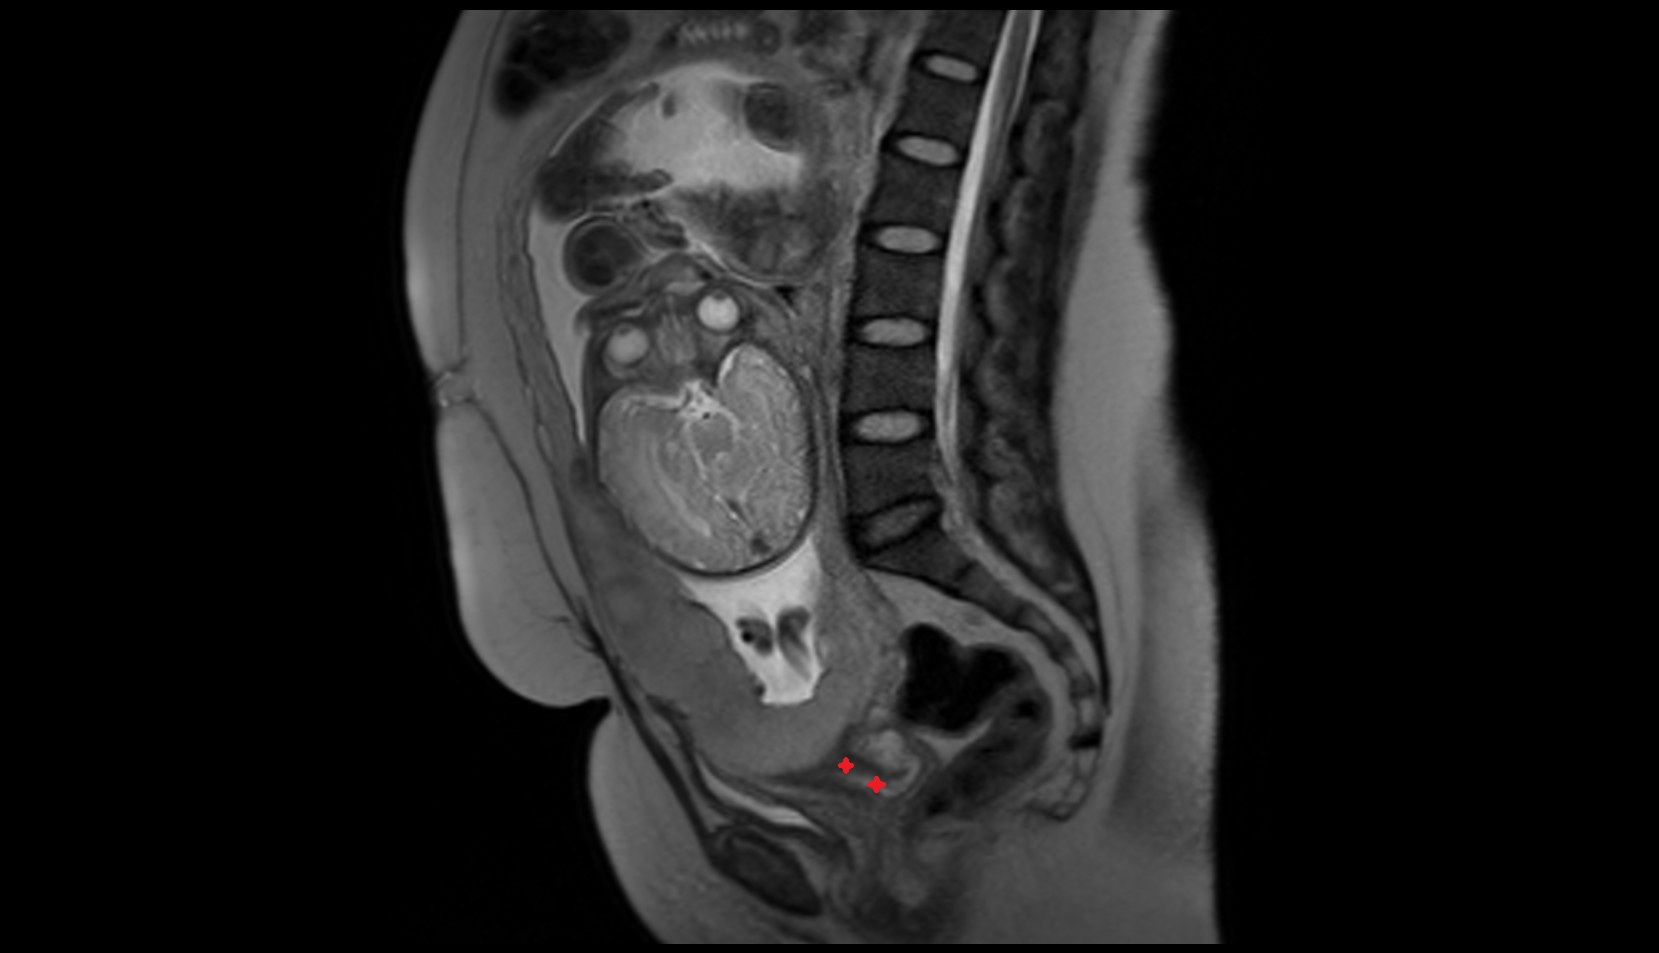

- Placenta

- Uterus (pregnancy)

- Amniotic fluid

- Umbilical cord

- Urinary Bladder in Pregnancy

- Cervix in Pregnancy

- Vagina in Pregnancy

- Fundus of uterus in pregnancy